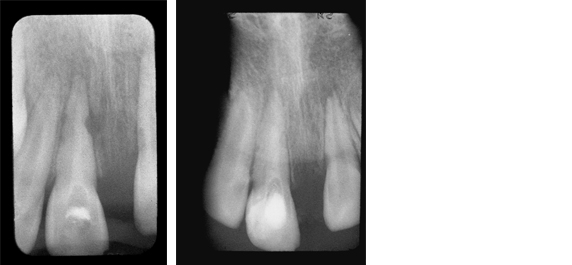

Dentin Bridge Formation

Case 1

This histological section stained with H & E shows new dentin bridge formation two months following pulpal curettage and treatment with Pulpdent Paste.

Case 2

The patient presented in pain with fractured upper central incisors and exposed pulps. Pulpotomies were performed using Pulpdent Paste as the pulpal dressing, which was sealed in place with zinc phosphate cement. Composite restorations were placed using pins for retention. One year after the pulpotomies, the patient returned for more esthetic composite restorations.

A radiograph taken after one-year shows two new dense dentin bridges with composites held in place with pins.

Fig. 1: This is a rare photograph of the new dentin bridges after removal of the composite, pins and zinc phosphate cement.

Fig. 2: Multi-Cal can also be used for dentin bridge formation in direct pulp capping, pulpal curettage and vital calcium hydroxide pulpotomy procedures.